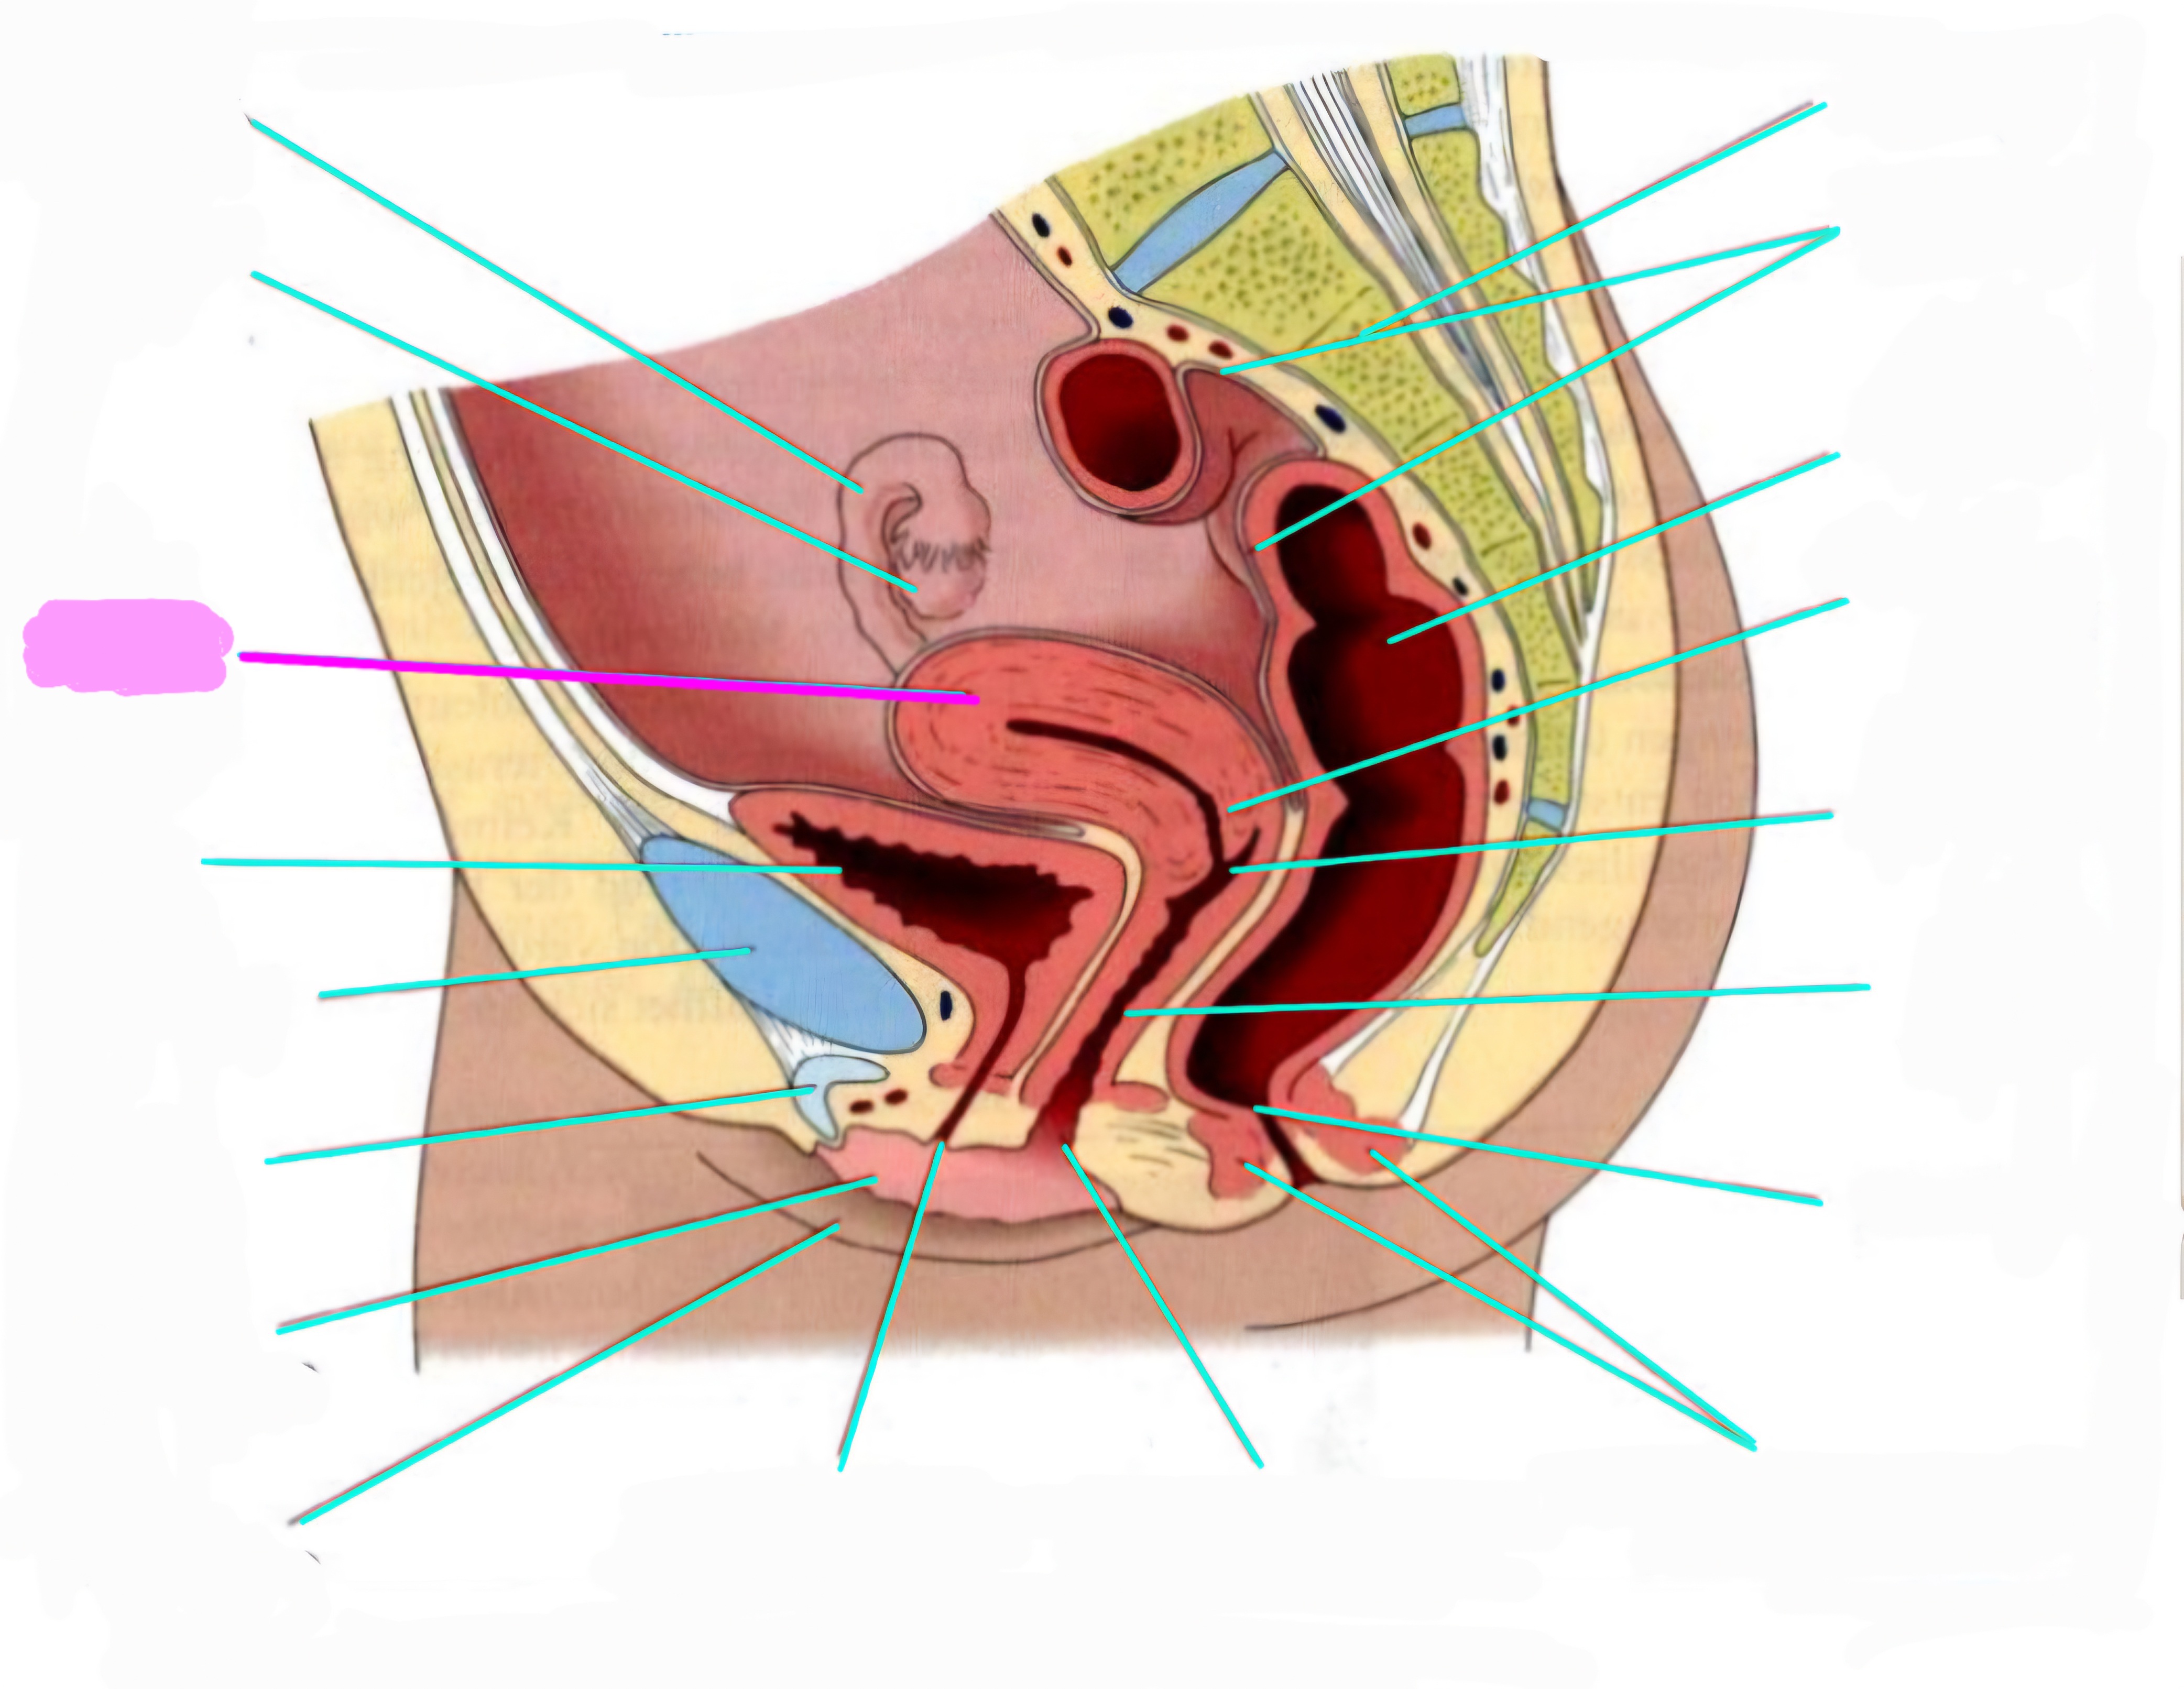

wbl. genital Anatomie

19 Terms

Tubea uterina (Eileiter)

Ovar (Eierstock)

Uterus (Gebärmutter)

Vesica Urinaria (Harnblase)

Symphyse

Klitoris

Labia minor pudendi (kleine schamlippen)

Labia Majoran pudendi (große Schamlippe)

Urethra (Harnröhre)

Introitus vaginae (Scheideneingang)

Sphincter ani externes (äußere Afterschließmuskel)

Anus (After)

Vagina (Scheide)

Portio (äußerer Muttermund)

Rektum (Mastdarm)

Zervix (Gebärmutterhals)

Peritoneum (Bauchfell)

Os sacrum (Kreuzbein)

Uterus: Topographie und Aufbau - wie groß ist er und wo liegt er?

7-8cm lang, Form einer umgedrehten Birne

Lage: im kleinen Becken zwischen Blase und Rektum

Antiversio: nach vorne geneigt, steht im Winkel zur Scheide

Antiflexio: in sich selbst geknickt, nach vorne abgebogen öber die Blase